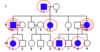

Pedigree of a mating between two

patients with achondroplasia